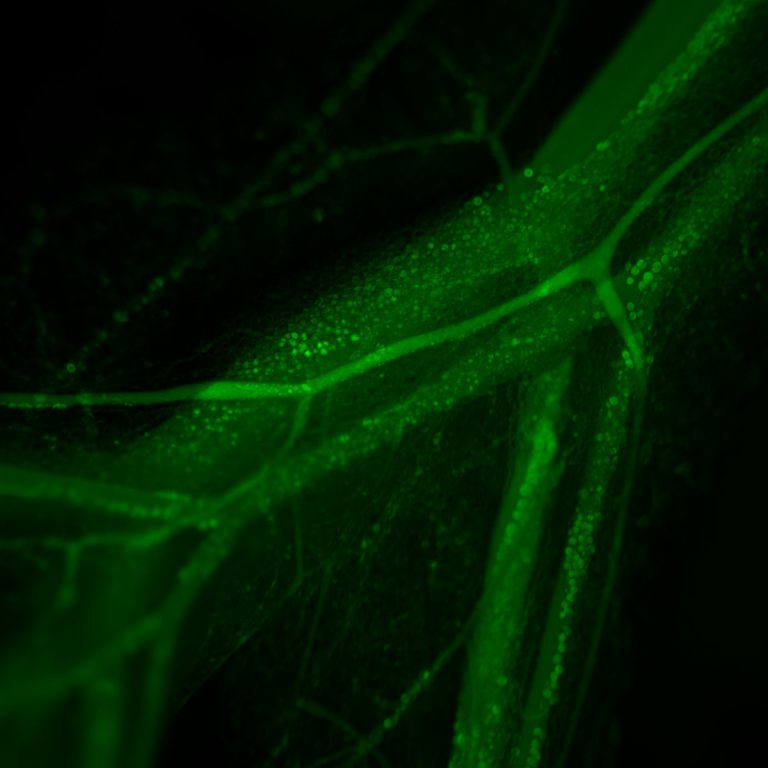

Is the observation of biological processes within the physiological context of a living specimen using a microscope. The model used is the Mouse vascular mesentery network. We studied Hyperpermeability in vivo, by topical application of Inflammatory agonists (PAF or VEGF) or by Ischemia-reperfusion injury (clapping the vessel). FITC-Dextran 70 is used as a macromolecular tracer (mimics Albumin). The representative image shows the mouse mesentery vascular network loaded with FITC-dextran 70.